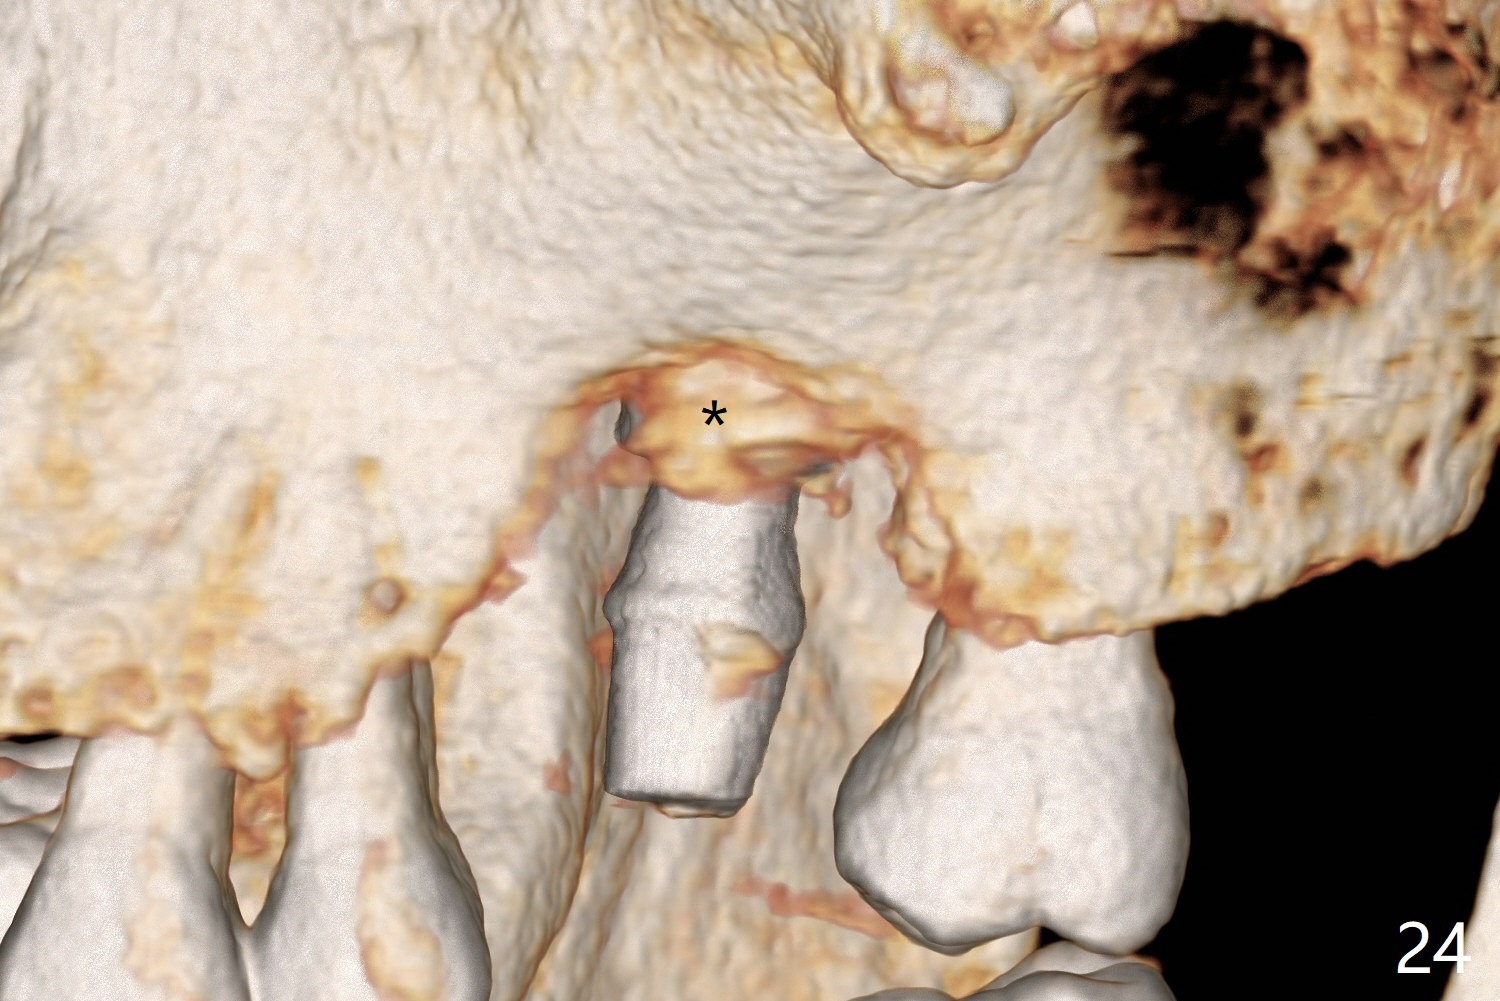

There is a mushroom around the implant nearly 5 months postop/immediately before cementation (Fig.21).  The bone density around the implant is low (Fig.22-24' *).